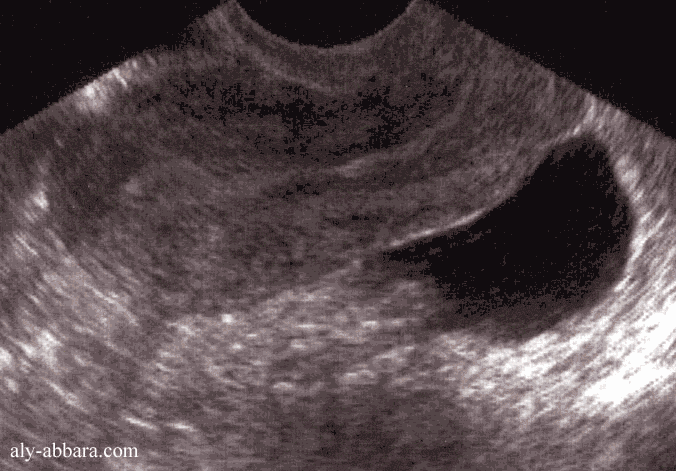

Cul-de-sac postétrieur (de Douglas) mis en évidence par la présence d'un épanchement

liquidien

à la suite de la rupture d'un petit kyste ovarien fonctionnel